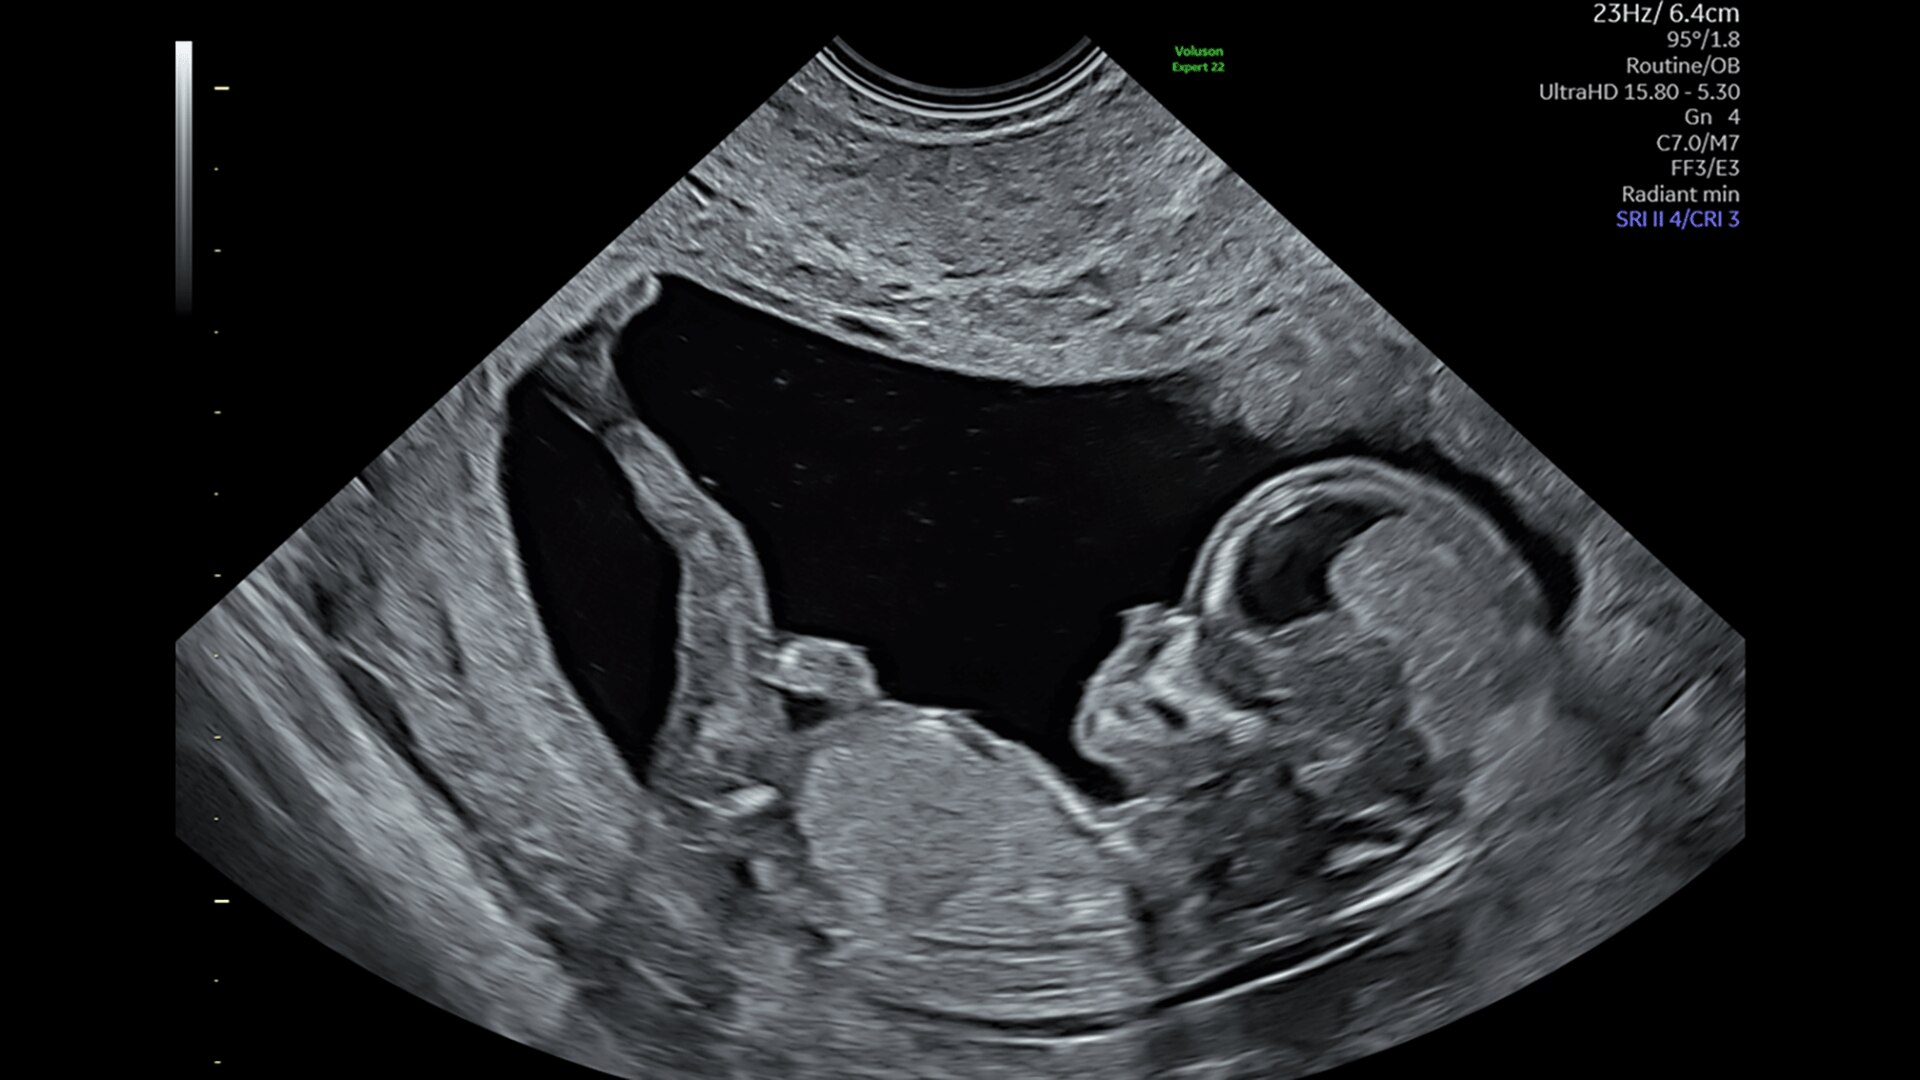

First Trimester Exams

Perform detailed exams with high-resolution for early insights to fetal health

Fetal Heart Assessment

Detect, diagnose, and monitor with confidence using Radiant and fetal HQ